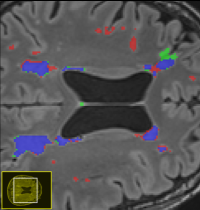

White matter hyperintensities (WMHs) are among the signs of vascular dementia on conventional MRI. In this thesis, relevant automated algorithms for segmentation of WMHs shall be compared for their performance on a clinical cohort.